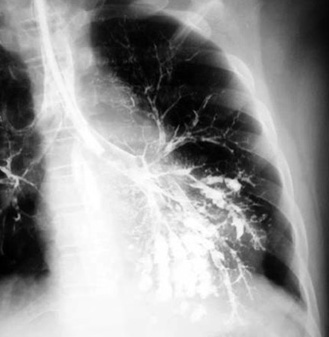

Localized Saccular BronchiectasisLeft hilum pulled down by the atelectatic left lower lobe. Retrocardiac tubular densities (hard to visualize). Bronchogram showing saccular bronchiectasis. Bronchograms are rarely done nowadays. CT can provide the diagnostic information. |